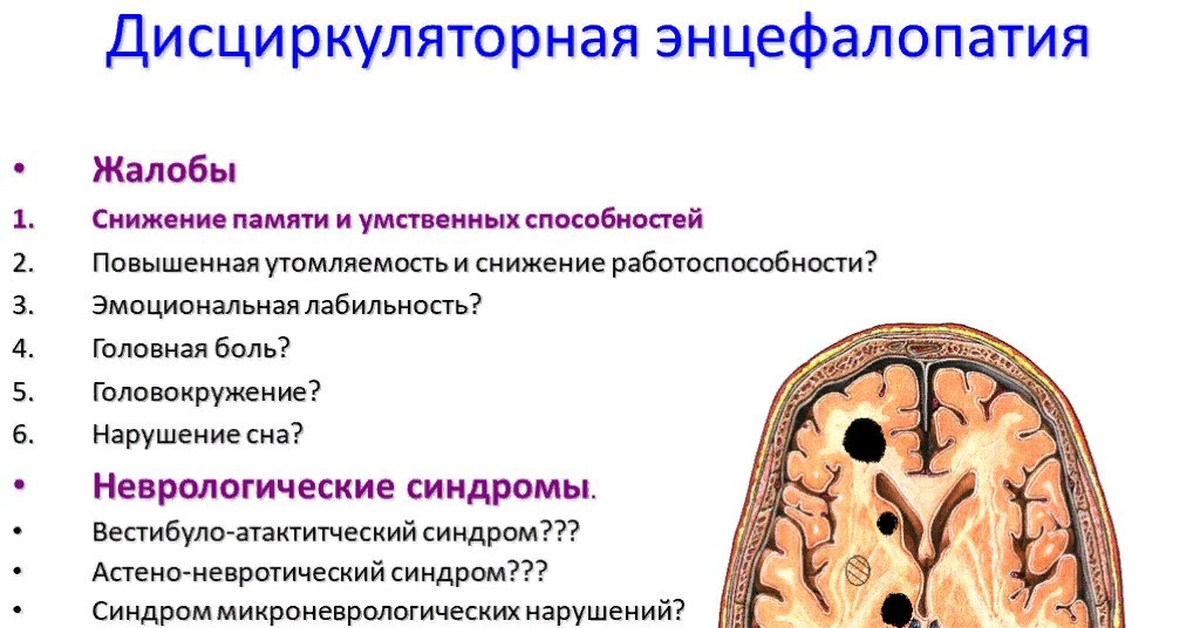

Пирамидная симптоматика в неврологии: ключевые аспекты